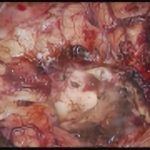

術中写真

摘出 前